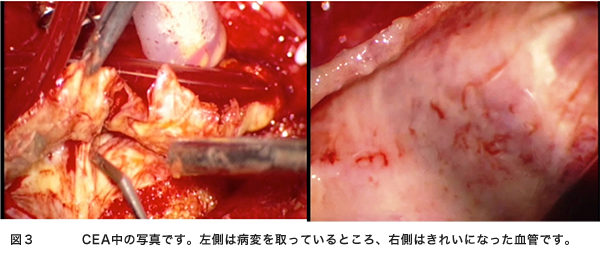

検査は頚動脈エコー、頸部血管MRA、または血管撮影などがあります。この検査の選択は各施設によって異なります。これらの検査で強い動脈狭窄が発見されたら患者さんと相談して手術治療を考えていくことになります。この手術を頚動脈内膜血栓摘出術(CEA)といいます。簡単に説明すると、動脈硬化で細くなった血管を広げて、脳梗塞の原因となる血の塊(血栓)を取り去ってしまう手術です(図1、図3)。現在最も安全性と治療効果に優れている方法です。この手術の適応で興味のあるところは施設の手術成績によって適応が決定されることです。症状が出現した内頚動脈狭窄症に対してはCEAの合併症が6%以下の施設での手術が有効性であるとされています。別の言い方をするとCEAの合併症が6%以上の施設、術者はこの手術をやってはいけないことになります。